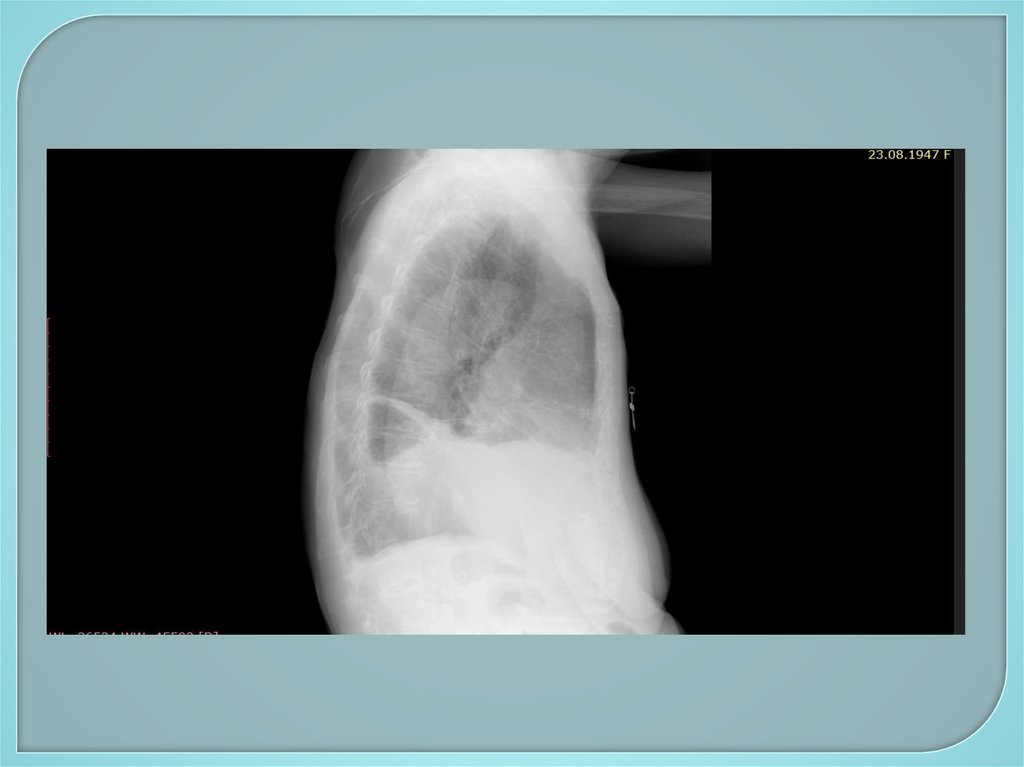

Двусторонний гидроторакс. Состояние

после протезирования митрального клапана